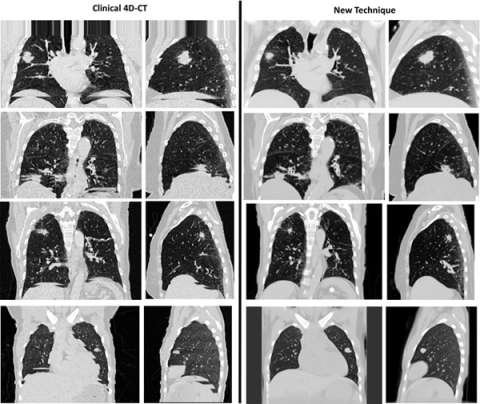

Accurate time-resolved imaging is crucial to the management of respiratory motion in radiation therapy treatment planning. Conventional techniques for producing breathing gated images commonly suffer from artifacts due to their inability to account for irregular breathing cycles. A novel CT acquisition and analysis technique, 5DCT, is utilized at UCLA in order to better inform treatment plan design for mobile tumors. Compared to current commercial protocols, 5DCT offers several advantages:

- Images do not contain artifacts that arise from the sorting of images performed by commercial techniques.

- Any number of images at user-selected breathing phases can be generated without altering the acquisition protocol.

- Resulting images are low-noise while patient dose remains similar to or less than current techniques, and the entirety of the imaging dose potentially contributes to image quality.

5DCT exploits standard fast helical acquisition with simultaneous breathing surrogate measurement, deformable image registration, and a breathing motion model to remove sorting artifacts. The accuracy of the motion model is assessed by reconstructing the original fast helical scans, which provide a ground truth.